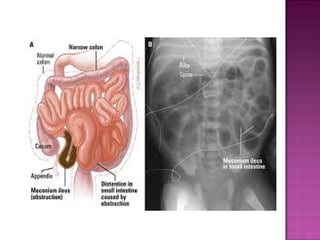

 LOW INTESTINAL OBSTRUCTION

distal ileum & colon.

LOW INTESTINAL OBSTRUCTION

 Due to intra uterine ischemic insult.

 Bilous vomiting & distention.

 Numerous dilated bowel loops.

 Meconium plugs obstruct colon & distal small

bowel.

 Associated with cystic fibrosis.

 AXR– multiple distended gut loops.

 Contrast study—meconium plugs & micro

colon.